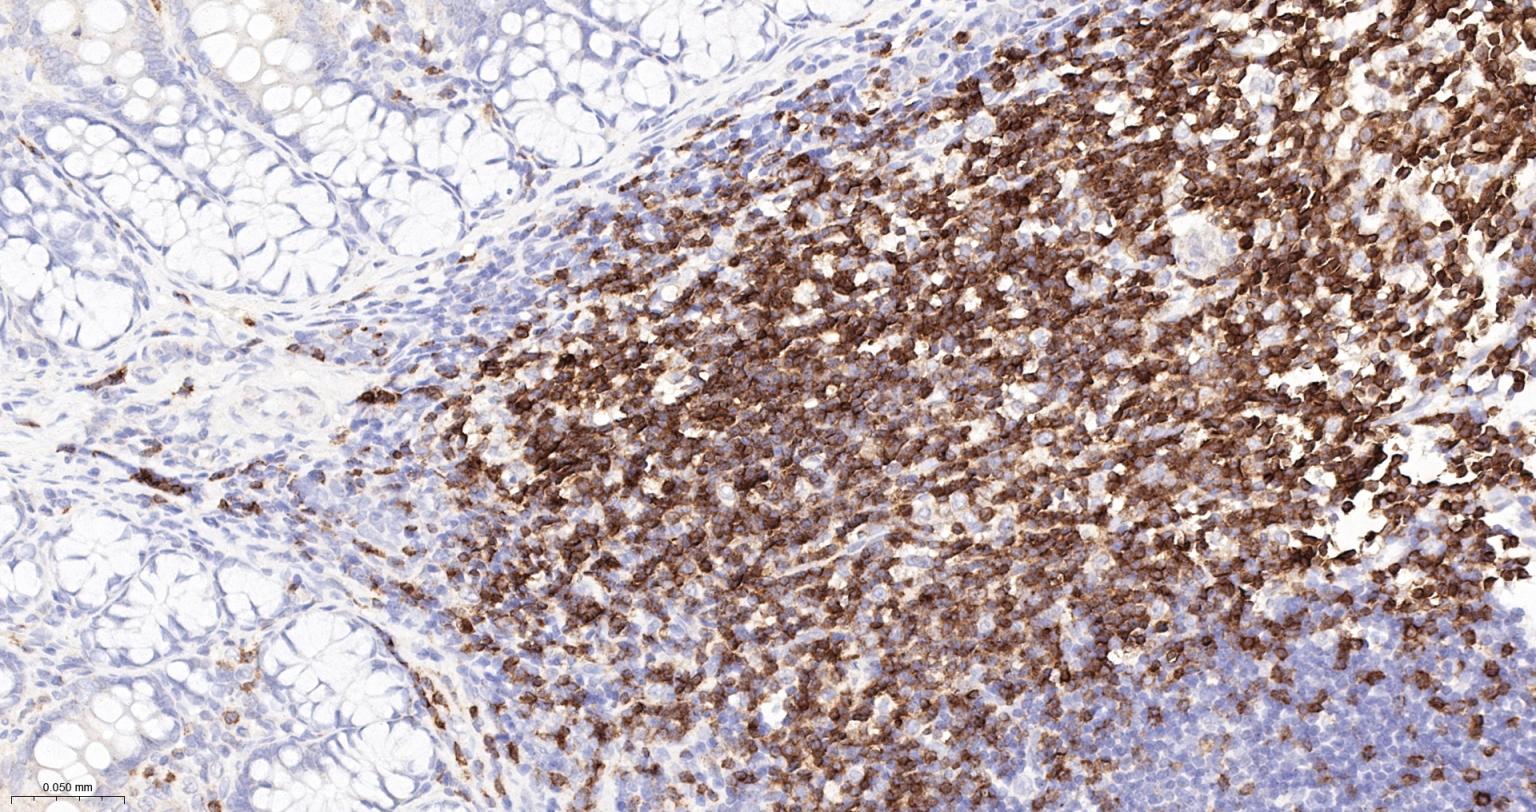

IHC-PHuman, Mouse, Rat1:500-2000